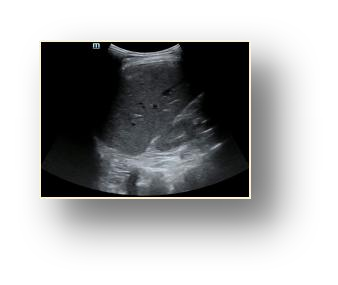

Most deep neural networks (DNNs) based ultrasound (US) medical image analysis models use pretrained backbones (e.g., ImageNet) for better model generalization. However, the domain gap between natural and medical images causes an inevitable performance bottleneck. To alleviate this problem, an US dataset named US-4 is constructed for direct pretraining on the same domain. It contains over 23,000 images from four US video sub-datasets. To learn robust features from US-4, we propose an US semi-supervised contrastive learning method, named USCL, for pretraining. In order to avoid high similarities between negative pairs as well as mine abundant visual features from limited US videos, USCL adopts a sample pair generation method to enrich the feature involved in a single step of contrastive optimization. Extensive experiments on several downstream tasks show the superiority of USCL pretraining against ImageNet pretraining and other state-of-the-art (SOTA) pretraining approaches. In particular, USCL pretrained backbone achieves fine-tuning accuracy of over 94% on POCUS dataset, which is 10% higher than 84% of the ImageNet pretrained model. The source codes of this work are available at https://github.com/983632847/USCL.

翻译:大部分深心神经网络(DNNS)基于超声波(美国)的超声波医学图像分析模型使用预先训练的脊椎(如图像网络)来进行更好的模型化分析。然而,自然图像和医疗图像之间的领域差距造成了不可避免的性能瓶颈。为了缓解这一问题,为在同一领域直接训练建造了一个名为US-4的美国数据集。该数据集包含来自四个美国视频子数据集的23 000多张图像。为了从美国-4中学习强健的特征,我们提议了美国半监督的对比学习方法,名为USCL(USCL),用于预培训。为了避免负面对子与有限的美国视频中丰富的地雷视觉特征之间的高度相似性,USCL采用了一种样品配对生成方法来丰富单步对比性优化所涉及的特征。关于一些下游任务的广泛实验显示了USCL对图像网络预培训和其他状态艺术预培训方法的优势。特别是,USCLU预先训练的骨架在POCS数据集上实现了94 %的微调精准性精确度,这在图像网络上比84%高10 %/MUSPASTASTASTRAIN premstrain practresmex pract press press rodustrismex sramduction sramduction sramduction sramduction surgles)。